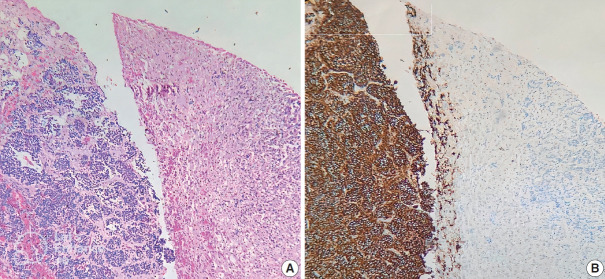

Methods: Ninety cases of NB at the Department of Pathology, University of Medicine and Pharmacy at Ho Chi Minh City, Viet Nam from 01/01/2018 to 12/31/2021, were immunohistochemically stained with ALK (D5F3) antibody. The ALK expression and its relations with some clinical and histopathological features were investigated.

Results: The rate of ALK expression in NB was 91.1%. High ALK expression (over 50% of tumor cells were positive with moderate-strong intensity) accounted for 65.6%, and low ALK expression accounted for 34.4%. All the MYCN-amplified NB patients had ALK immunohistochemistry positivity, most cases had high ALK protein expression. The undifferentiated subtype of NB had a lower ALK-positive rate than the poorly differentiated and differentiated subtype. The percentages of ALK positivity were significantly higher in more differentiated histological types of NB (p = .024). There was no relation between ALK expression and: age group, sex, primary tumor location, tumor stage, MYCN status, clinical risk, Mitotic-Karyorrhectic Index, prognostic group, necrosis, and calcification.